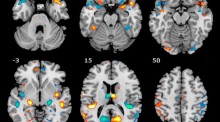

Stimulant drugs trigger transient volumetric changes in the human ventral striatum Elseline HoekzemaSusana CarmonaOscar Vilarroya Original Article 27 November 2012 Pages: 23 - 34